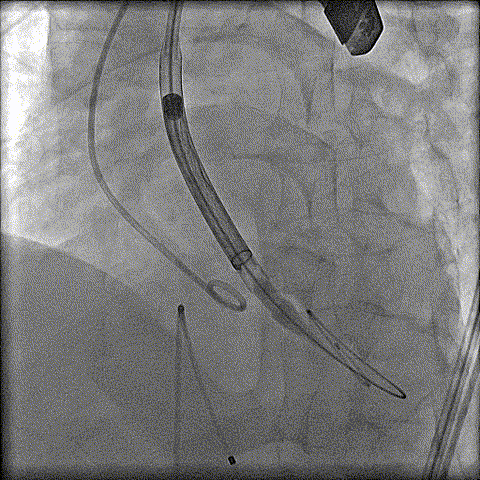

预扩

猪尾中部释放

稳定回收

评估

最终释放

后扩

无瓣周漏